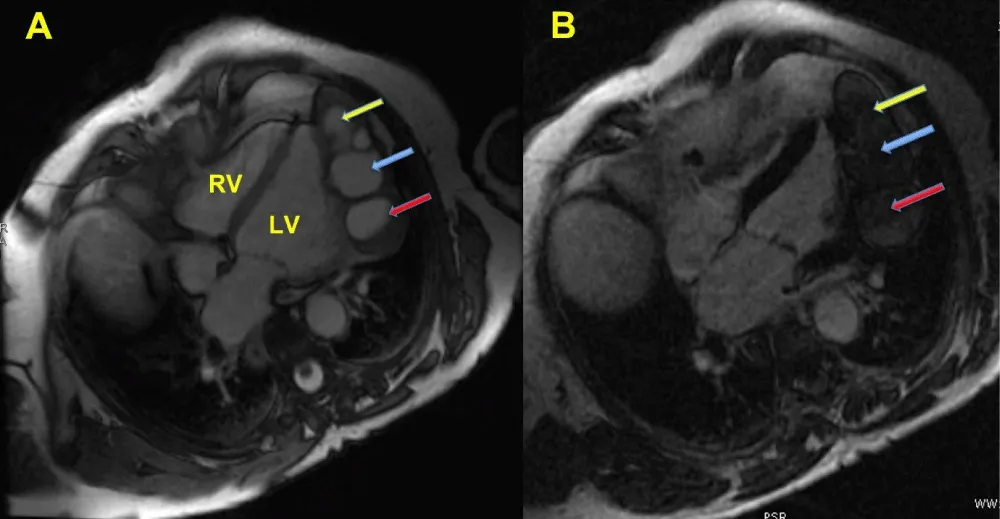

Considering the patient’s case history (farmer), it was suspected the presence of hydatid cysts. Consequently, the serologic test (hydatid cyst antibody), and enzyme-linked immunosorbent assay (ELISA) were also unremarkable and we decide to perform cardiac magnet resonance (CMR). CMR imaging evidenced three large pericardial cysts along with a smaller cyst, respectively placed on the side wall of the left ventricle (Figure 1A, Clip 1). Cysts were adherent to the pericardial visceral layer and they slightly influenced the heart sidewall movement.

On T1W1 images, the lesion appeared hypo- to iso-intense and it had no post-contrast enhancement. After the gadolinium injection, it had been displayed both the pericardial cysts’ location (without perfusion) and the mild interference on the left ventricular wall movement (Figure 1B, Clip 2).

Figure 1: A: the CMR imaging shows the pericardial location of the cysts (blu arrow) at the level of left ventricular lateral wall. CMR well depicted three large cysts and one smaller cyst (Clip 1). B: LGE shows no uptake of pericardial cysts (arrows), close to left ventricular lateral wall (Clip 2). Pericardial cysts characteristically do not enhance with administration of gadolinium.LV: Left Ventricle; RV: Right Ventricle; CMR: Cardiac Magnetic Resonance; LGE: Late Gadolinium Enhancement.